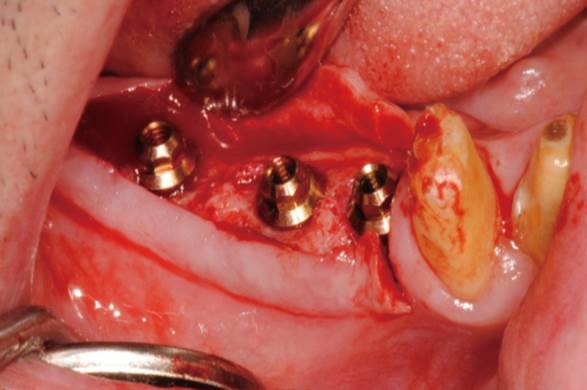

Clinical case: Extraction of all teeth in upper maxilla,

immediate implant placement, & provisionalization

- Courtesy of Dr. Iulian Filipov, Romania -

Keywords

AnyRidge, immediate placement, immediate provisionalization, maxillary fully edentulous case, initial stability, edentulous, Dr. Iulian Filipov, R2GATE, MEGA ISQ

Products:

AnyRidge implant system, Mega ISQ, R2GATE